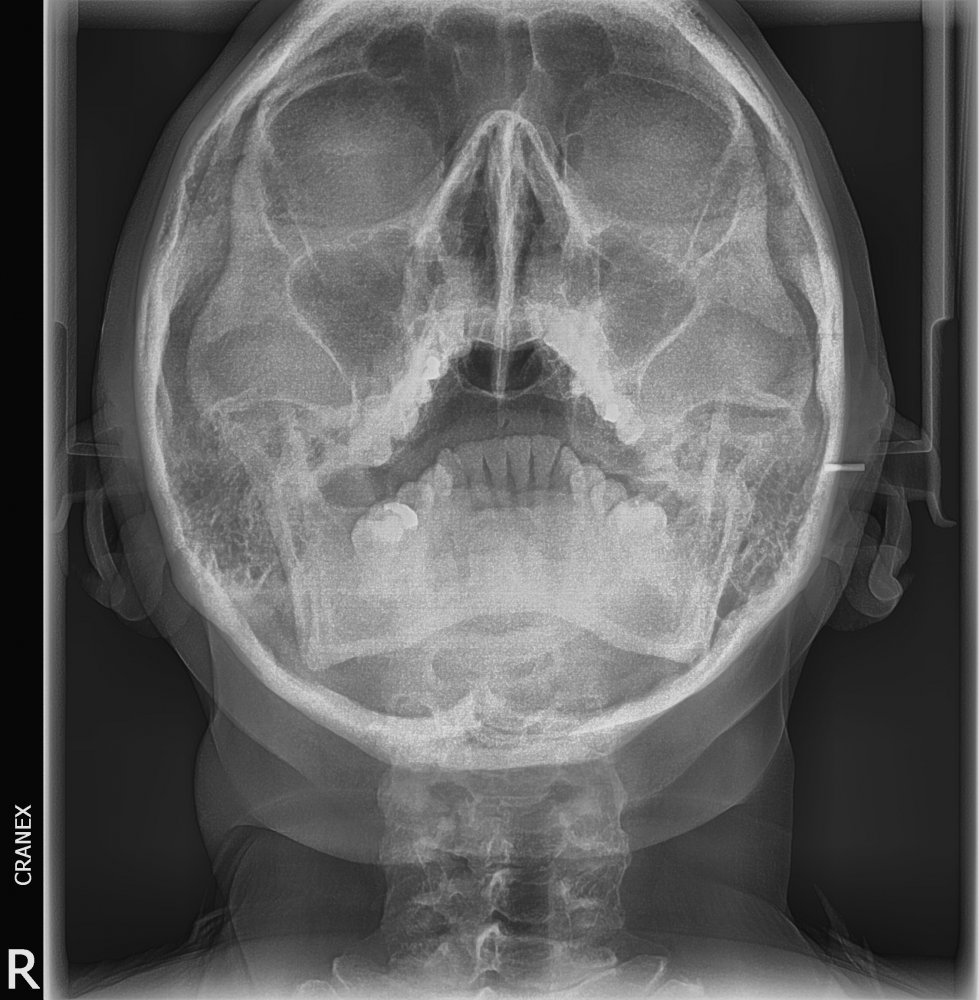

Radiografías Extraorales CRANEX

Caso Radiográfico N° 06 Sinusitis de seno maxilar en relación a comunicación buco sinusal CRANEX

Radiografía de Cadwell. Radiografía de Waters. 2.- Forma de realización del examen . Como toda radiografía, se toma en la sala de rayos. Se le pide al paciente que se siente en una silla, que mire hacia delante y fije su cabeza y se toma la proyección antero-posterior.. Estudio de la identificación de las distintas estructuras que podemos describir en una Rx de cráneo (water)